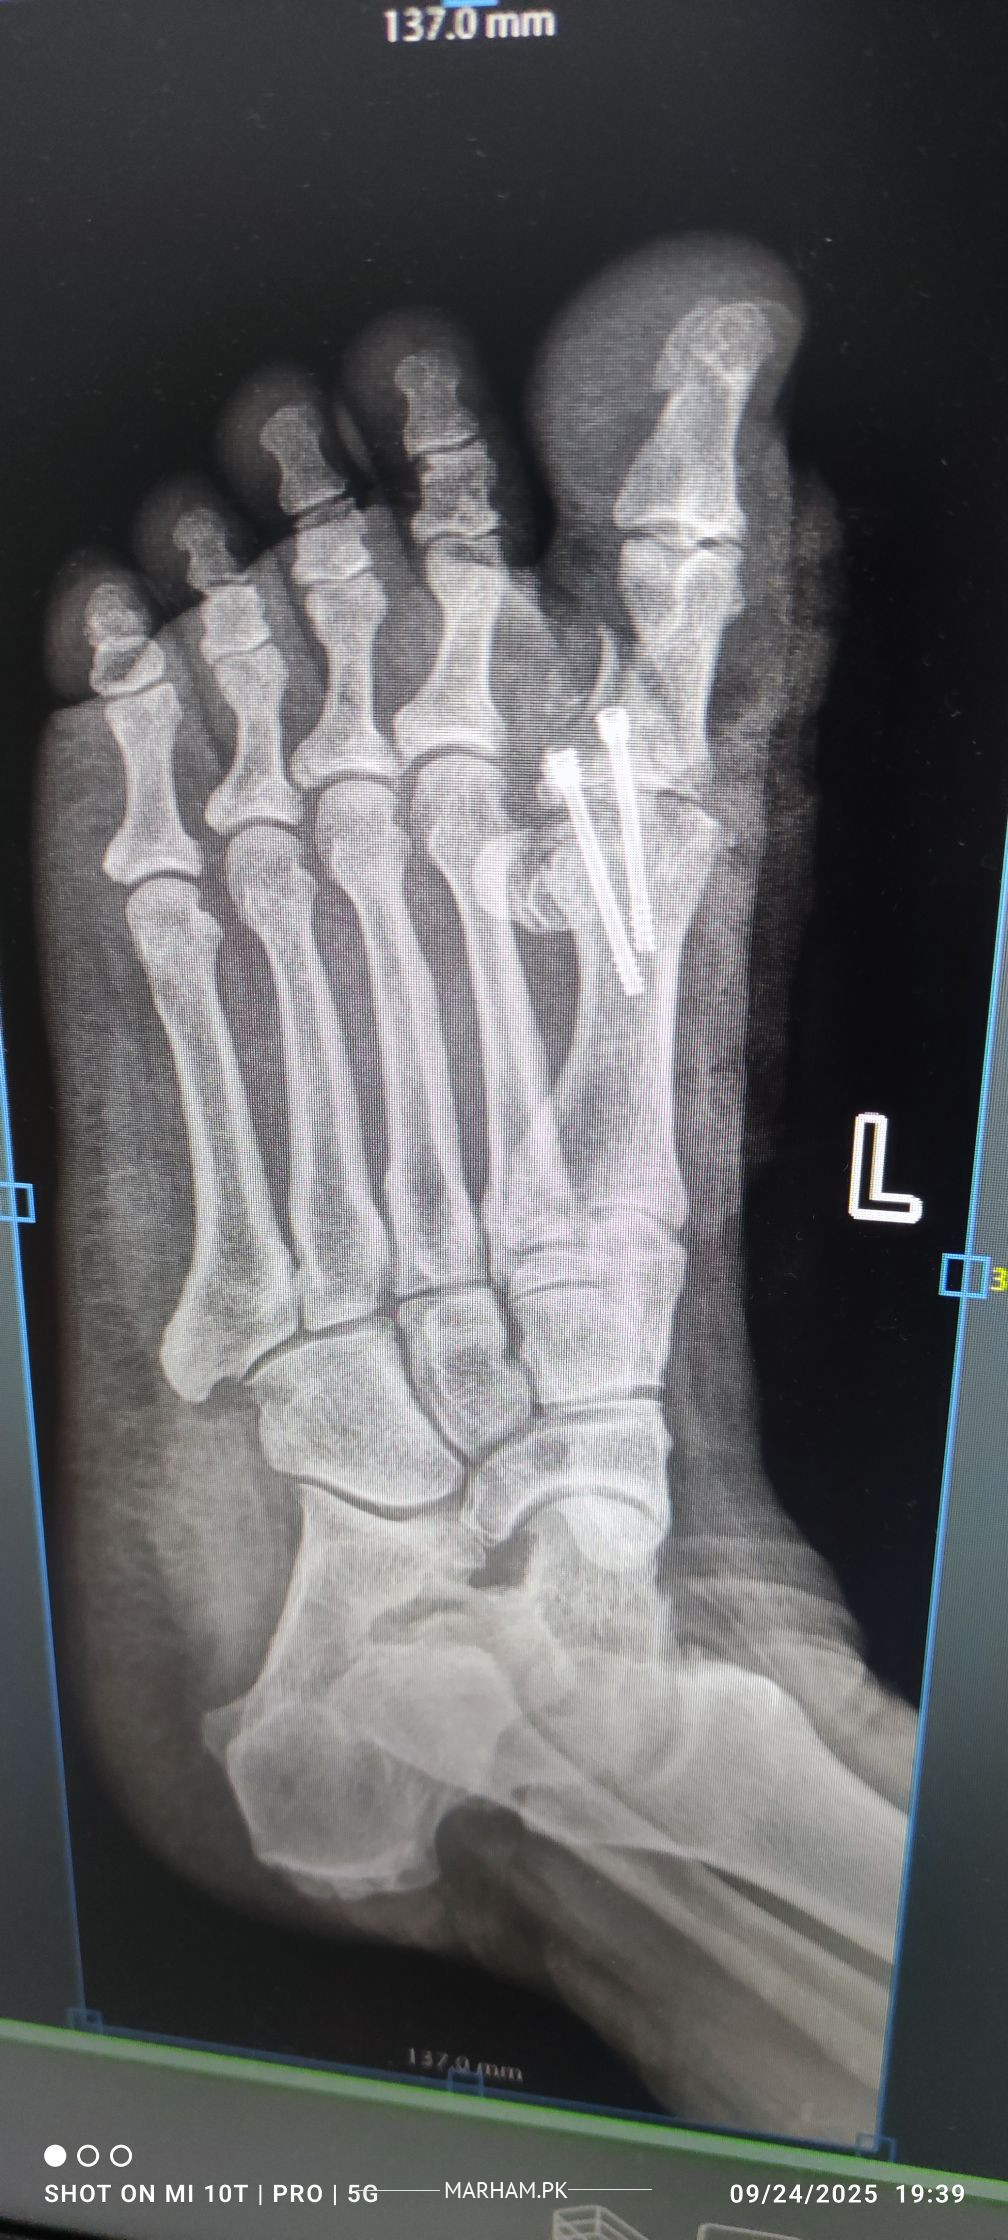

AoA, kindly ye meri mother ki xray report daikh kar bta dain k operation theek ho gya hai, X-ray main fracture nazar aa rha hai lekin, technician ny b kaha k fracture show ho rha hai kisi doctor ko dikha dain. shukria

Need following informations

1- Date of injury or weeks

2- XRay before Surgery

3- XRay just after surgery

4- XRay latest , you already shared

Regards

Osteotomy means cutting the bone to straighten it, usually to relieve pain or improve joint function. After the cut, the bone is held in place with plates, screws or pins while it heals. Most people need a period of limited weight‑bearing followed by physical therapy to rebuild strength and range of motion. Recovery can take several months, and the goal is to return to normal activities, but some patients may still need braces or activity adjustments. The procedure is common for knee, hip or foot problems, and outcomes are generally good when the surgeon’s plan matches the patient’s anatomy and the rehab is followed closely. If you’re considering it, talk to an orthopedic surgeon about your specific condition, the expected healing time, and any lifestyle changes that will help you recover fully.